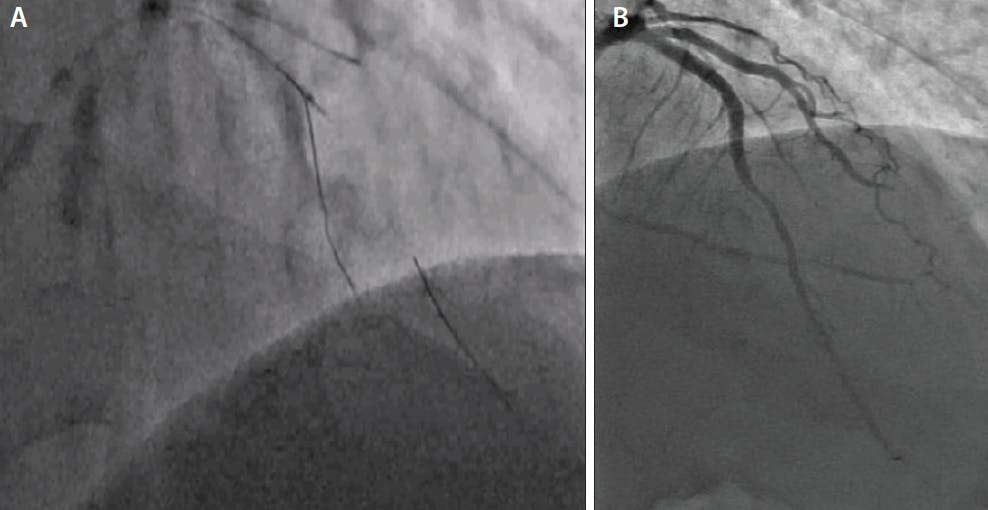

Figure 2. Still frame depicting successful wiring of a LAD artery CTO using the Sasuke DLM (A). Final results after successful CTO intervention with bifurcation stenting to the LAD and diagonal (Video 2) (B).

One of the most unfavorable anatomic features for antegrade CTO PCI is having a side branch adjacent to the proximal or distal caps.6 Use of a DLM can assist in improving precise manipulation of the guidewire into the proximal cap. A DLM is advanced in a side branch until the lateral port is at the level of the proximal cap. A CTO dedicated guidewire can then be advanced through the OTW lumen to engage the occlusion. This not only allows precise handling of the CTO guidewire but also enhances backup to facilitate the proximal cap puncture. Additionally, because it is positioned in the OTW lumen, the CTO dedicated guidewire can be advanced safely up to the level of the proximal cap.8 A DLM can be used when a CTO wire reenters a branch at the distal cap. The OTW lumen can be positioned to allow true lumen wiring or antegrade dissection reentry into the main vessel. An example of use of DLMs for main vessel access after CTO wired into a side branch is presented in Figure 1 and Figure 2.